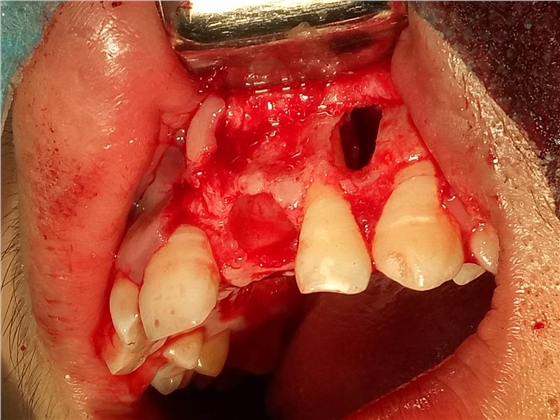

死髓牙2度,沒保留價值了,外傷造成的外吸收,即使到充也容易出問題。和患者溝通,要求做種植,用了兩個骨膠原,側切、尖牙沒事,側切做了一次根充